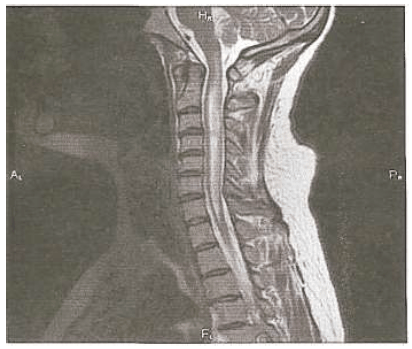

Há dois meses, paciente do sexo masculino, 45 anos, desenvolveu perda de visão quase completa no olho esquerdo, que não se resolveu apesar do uso de pulsoterapia com solumedrol, acompanhado por um ciclo de esteroides orais que foram progressivamente retirados. Duas semanas atrás, ele desenvolveu perda visual no olho direito, que persistiu. Relata parestesias com queimação em ambos os pés e alguma urgência urinária, ambas presentes há 1 ano. A RM da medula cervical é apresentada abaixo. Seu líquido cefalorraquidiano demonstra 50 leucócitos/mm3, com 45% de neutrófilos, 55% de linfócitos, proteína de 75 mg/dL e bandas oligoclonais negativas. O VDRL no LCR é negativo, HTLV I e II são negativos e o nível de vitamina B12 é normal. A ANA é moderadamente elevada em um título de 1:128.

De acordo com o exposto, qual seria o diagnóstico mais provável?